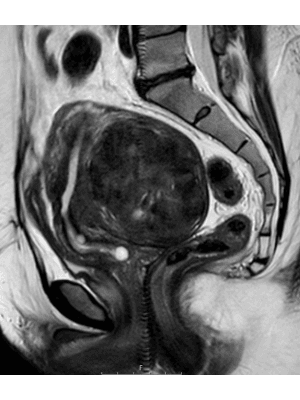

Fibroids, or leiomyomas, are defined as non-cancerous growths that develop within the uterus, composed of muscle and fibrous tissue. They are the most common tumour affecting women of reproductive age, and their prevalence increases with age. By the age of 50, almost 70% of Caucasian women and over 80% of Afro-Caribbean women will have had at least one fibroid. Fibroids can vary in size and location within the uterus and can affect any region along the anatomical spectrum of the outer serosal layer, the intramural myometrial layer and submucosal endometrial layer.